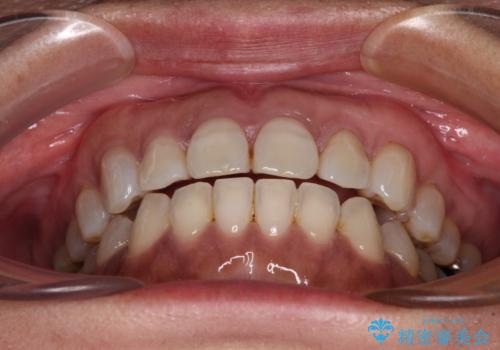

極端な上下前歯の開咬を改善 オープンバイトのインビザライン矯正

治療前に、いくらインビザライン矯正がオープンバイトを得意としているとは言え、さすがに限界があるだろうと思っておりましたが、前歯でレタスが噛めるまで改善することができました。

顔の印象も大きく変わり、患者様には大変満足していただきました。